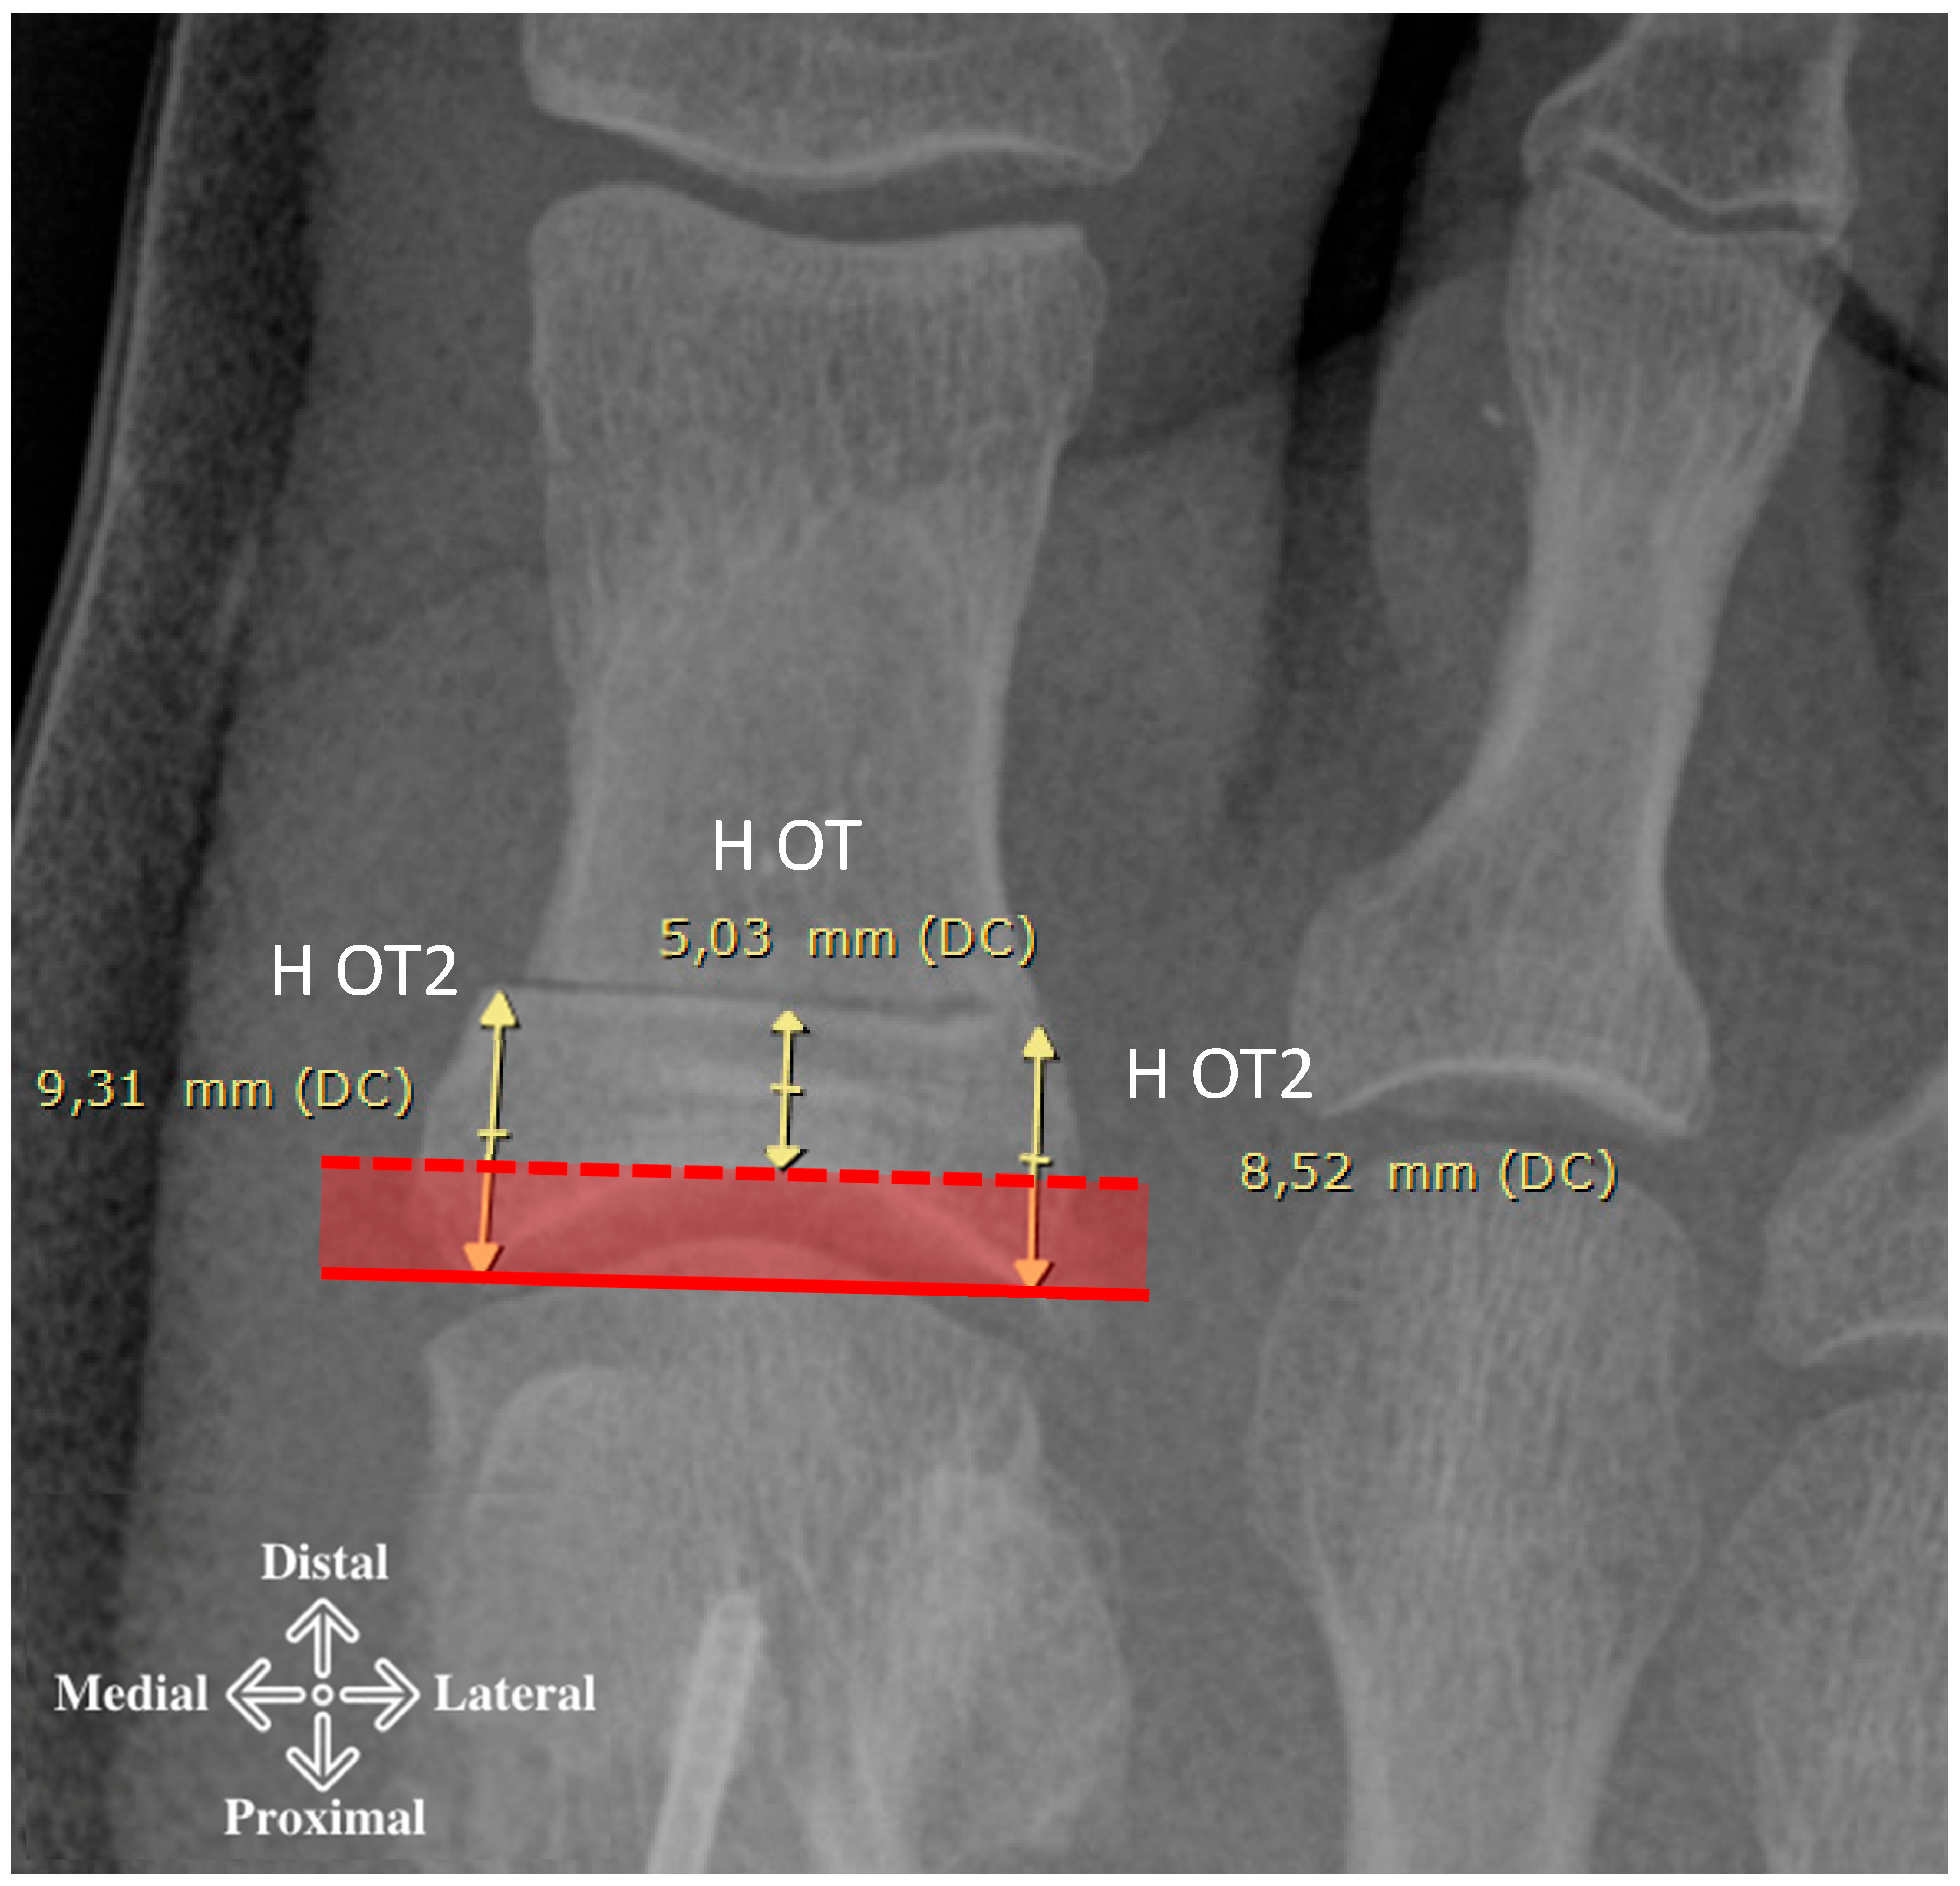

| HOT, mm | 5.14 | 1.45 | 1.57 | 8.08 | Osteotomy Height |

| H2OT, mm | 8.91 | 1.50 | 5.38 | 12.85 | |